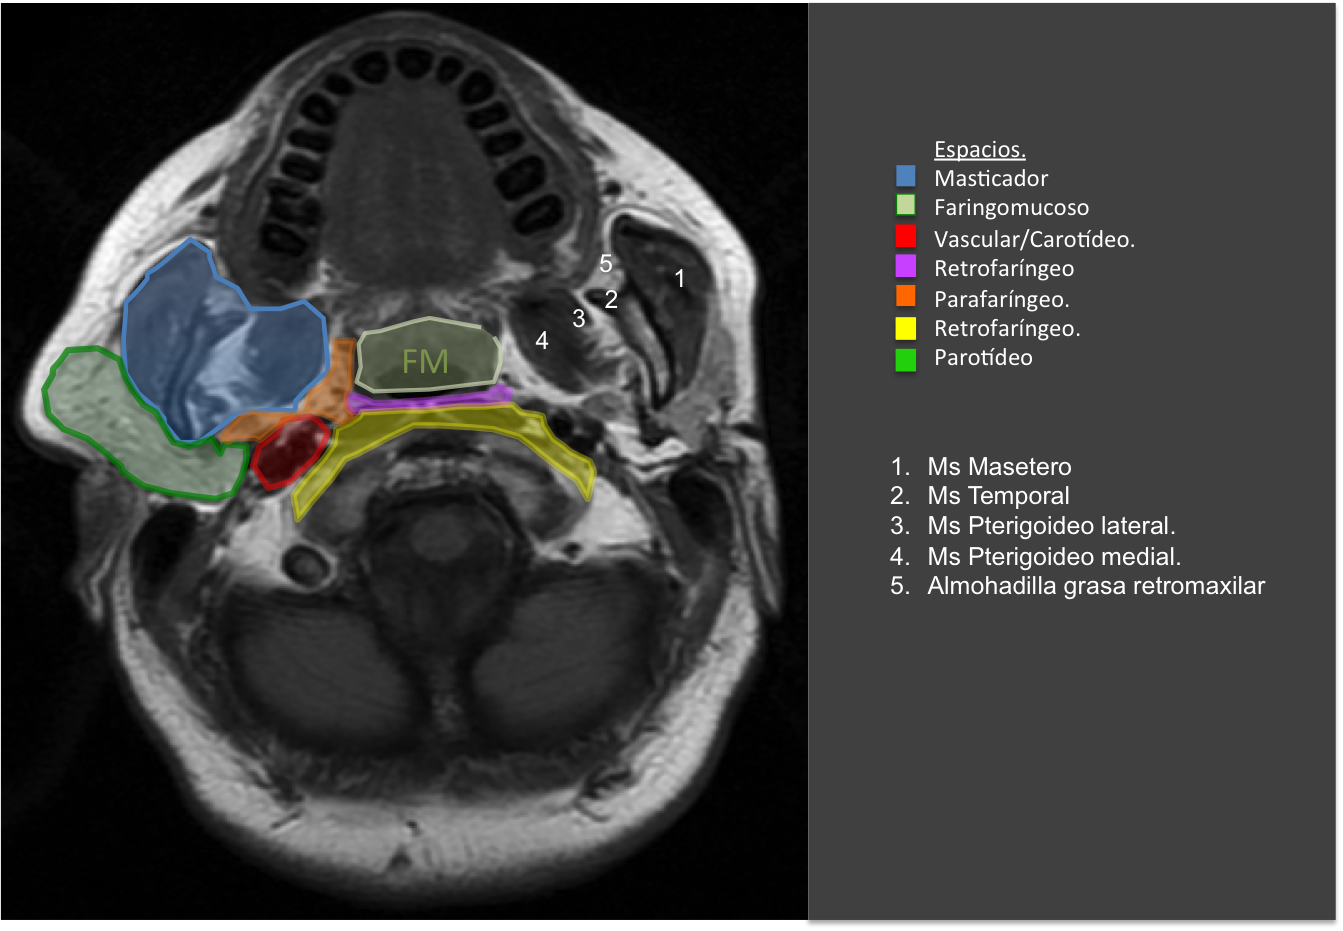

– Cuello suprahioideo se define como el conjunto de espacios situados en la fascia profunda por encima del hueso hioides: espacio parafaríngeo, espacio de la mucosa faríngea, espacio masticador, espacio parotídeo, espacio vascular (o carotídeo), espacio retrofaríngeo y espacio perivertebral.

ESPACIO PARAFARÍNGEO.

En este espacio importante donde encontraremos mucosa y tejido linfático. Esta región puede ser el foco de origen de procesos infecciosos como faringitis, amigdalitis y/o abscesos.

Amarillo: mucosa faringea/amígdala.

Rojo: espacio vascular.

Azul: espacio masticador.

Verde: espacio parotídeo.